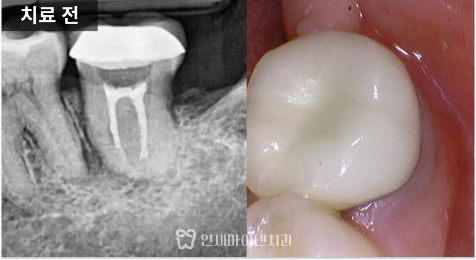

우선 잇몸은 깨끗한

편이었습니다.

염증은 없었지만

계속된 통증이 있는

상황이었습니다.

신경치료를 받은

치아 주변을 보면

까맣게 보입니다.

엑스레이를 확인해 보니

J자 모양으로 뼈가 녹아 있는

모습이 관찰되었습니다.